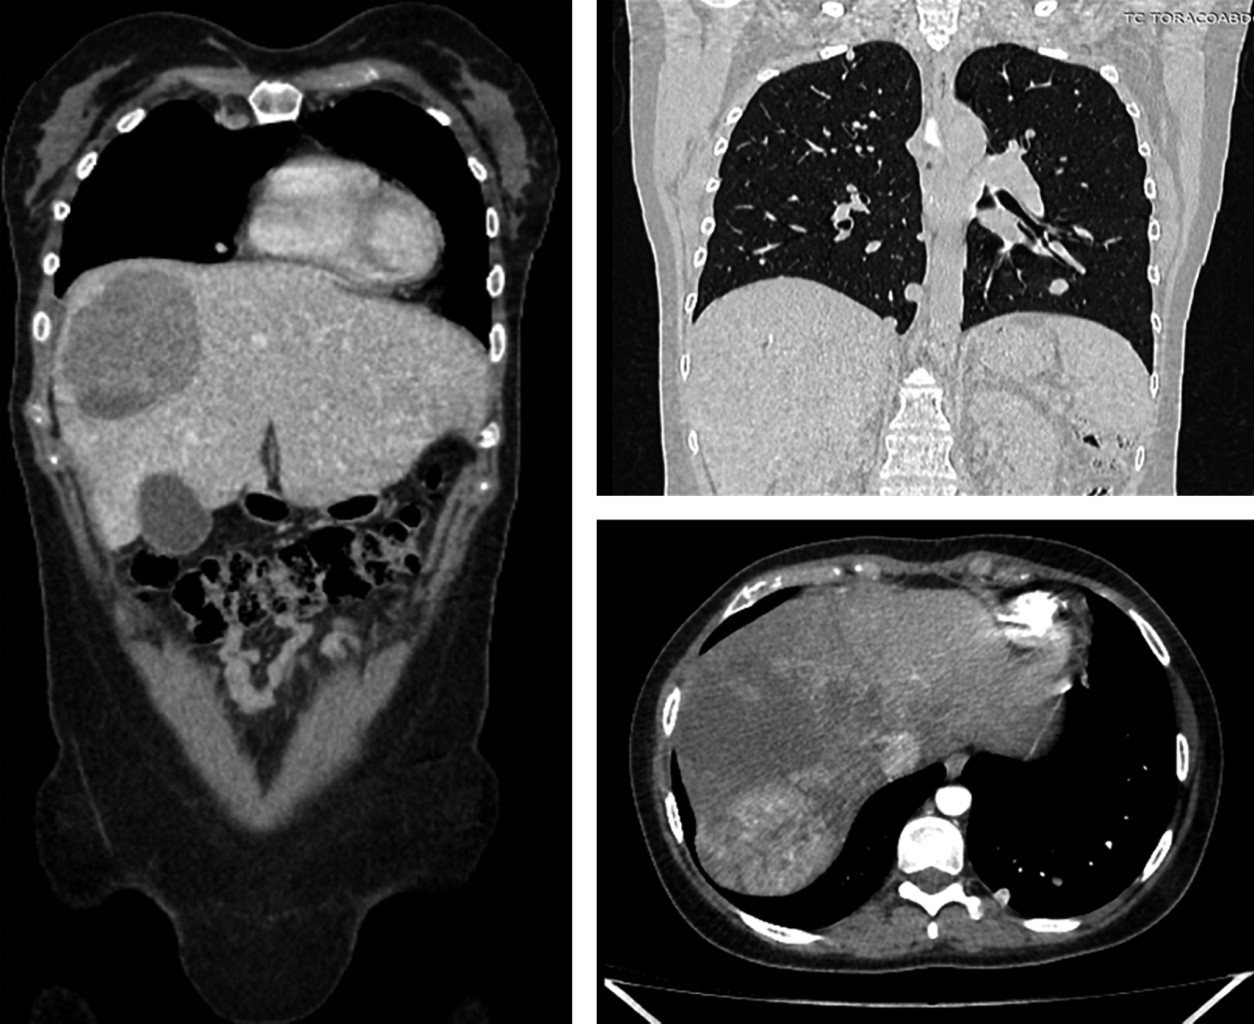

Introduction: fibrolamellar hepatocellular carcinoma (FLC) is a rare form of hepatocellular carcinoma affecting young patients. We present a case of unresectable FLC treated with transarterial chemoembolization and a combination of atezolizumab and bevacizumab. Case description: a 20-year-old woman with abdominal pain, nausea, and vomiting was diagnosed with well-differentiated FLC. A dual therapy regimen was implemented, achieving a 26.7% reduction in lesion size, maintained for 18.13 months. The overall survival was 22.23 months. Conclusion: FLC differs from conventional hepatocellular carcinoma and presents therapeutic challenges. The combination of chemoembolization and immunotherapy shows promising potential. This case adds valuable information about FLC in our country.

Figure 1